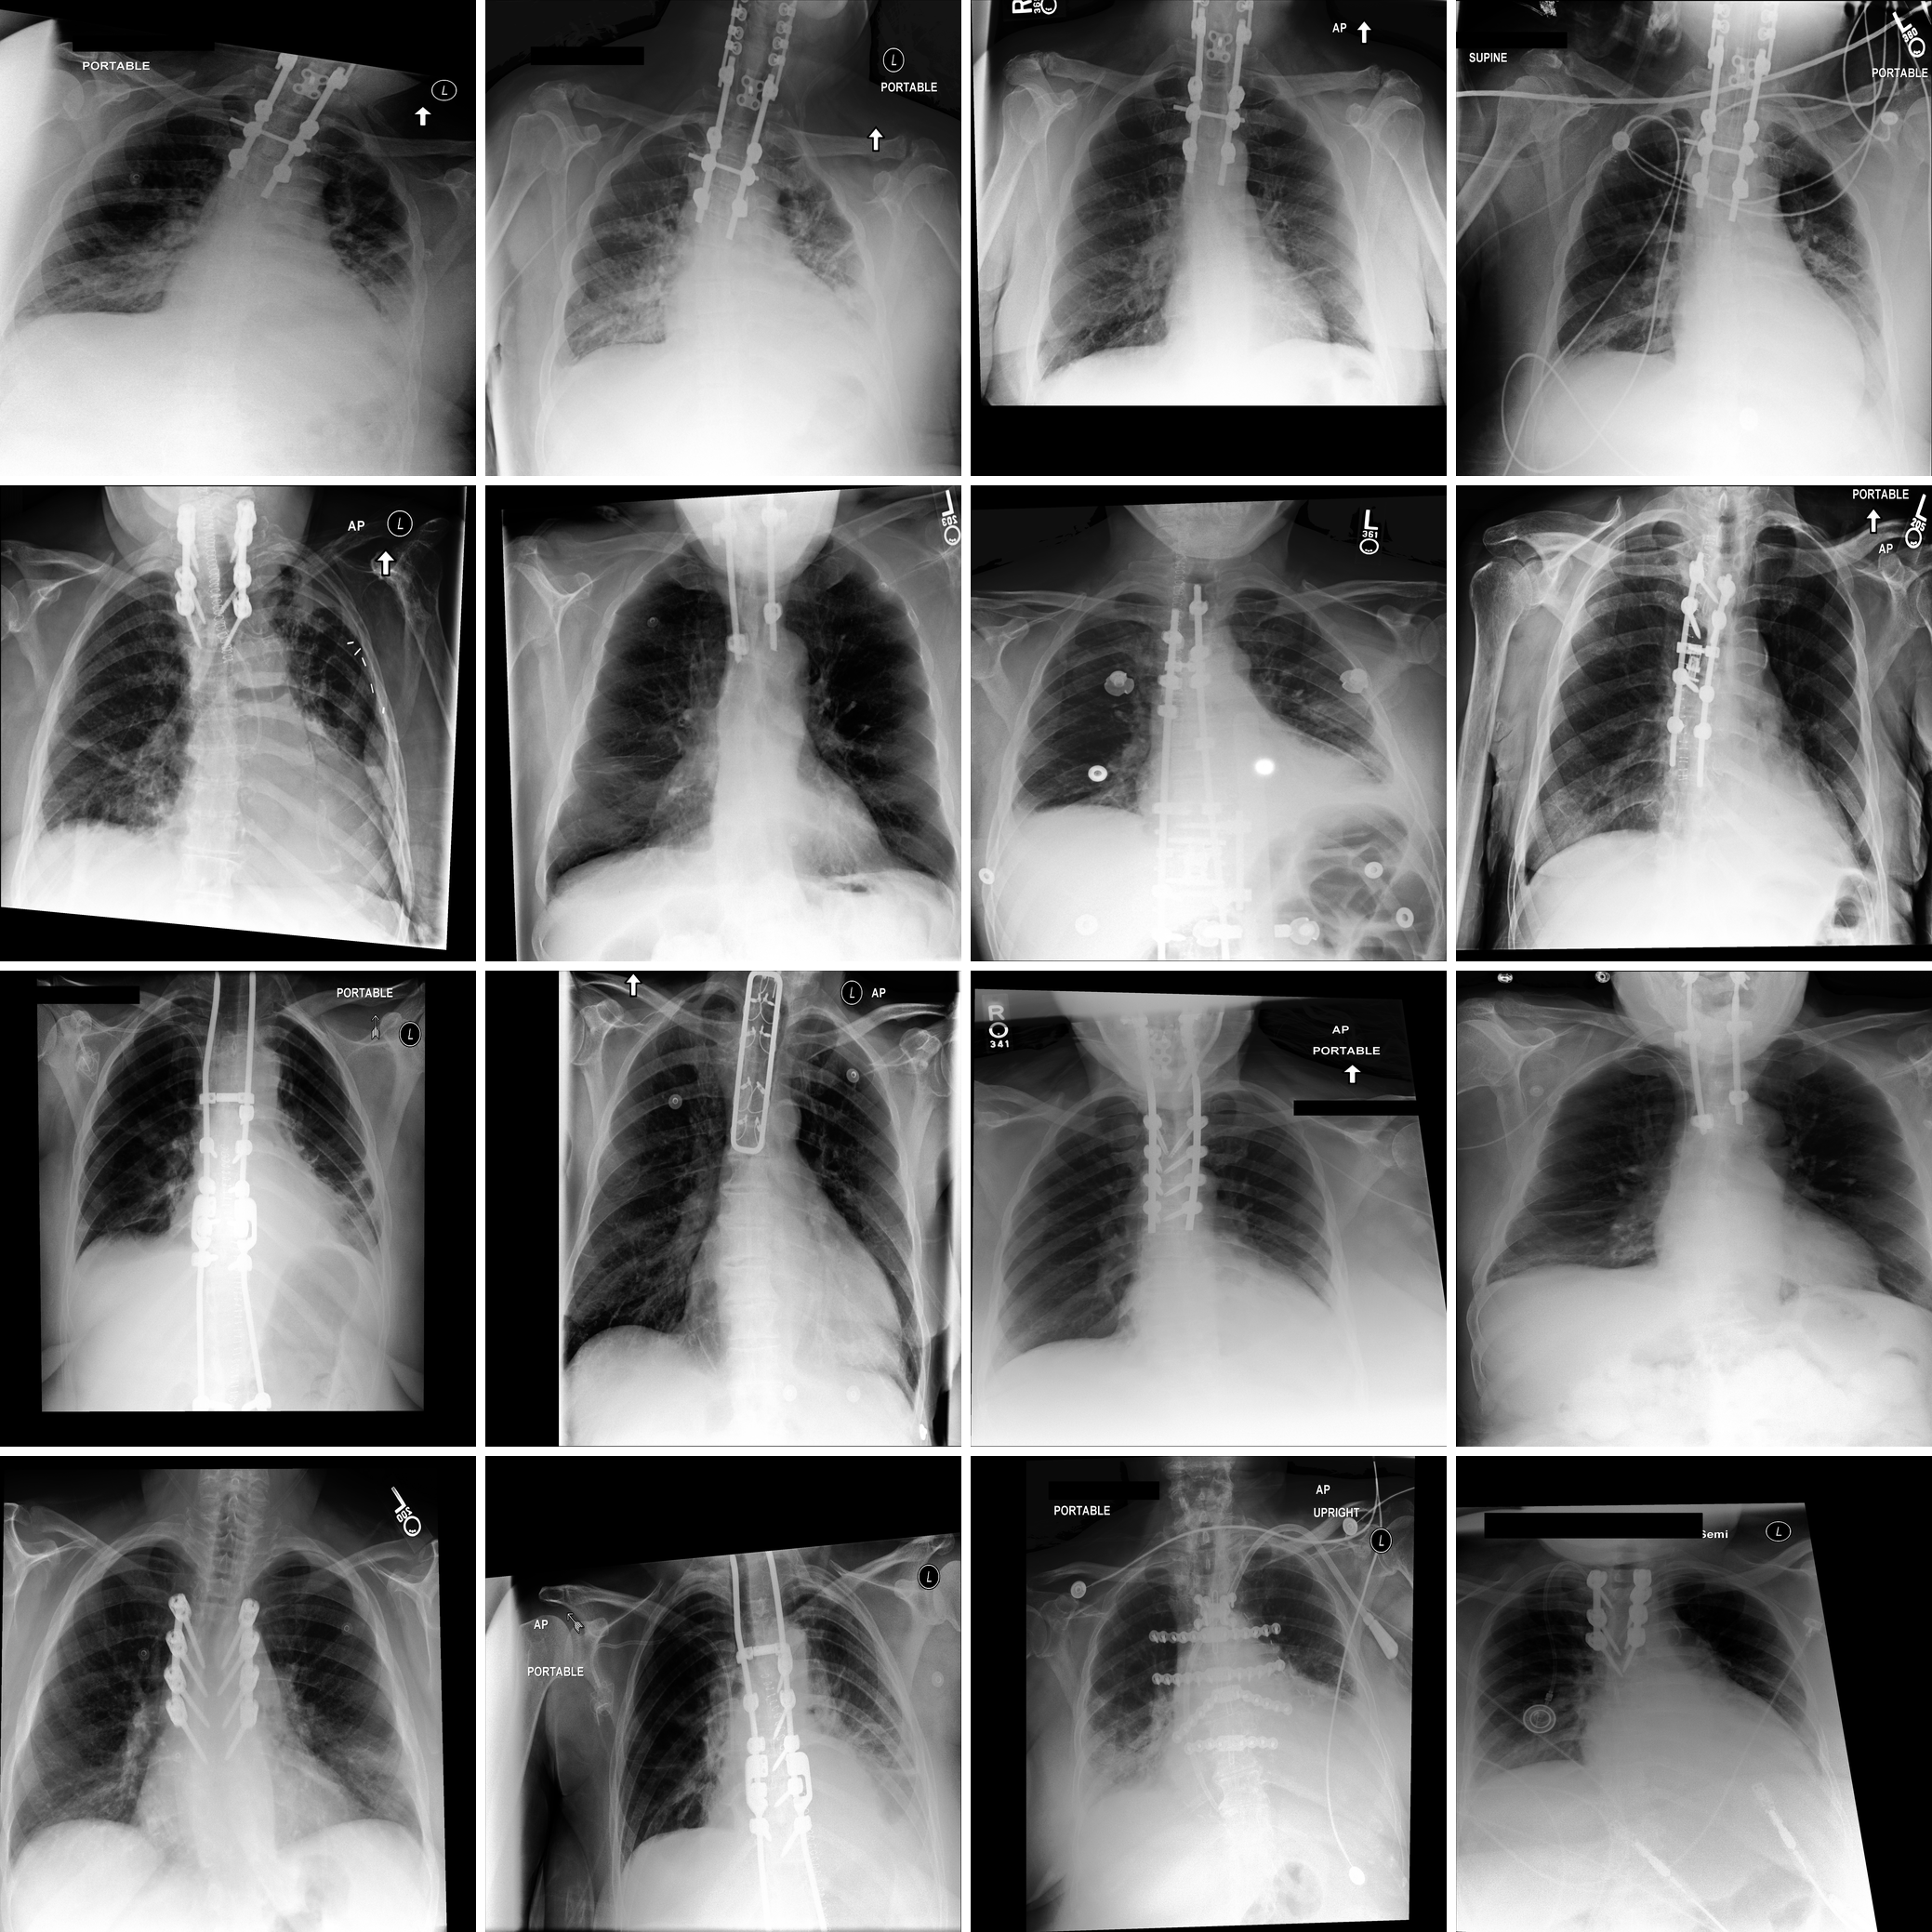

Refer to caption

Figure 2: SAE-Rad identifies clinically relevant and interpretable features within radiological images. We illustrate a number of pathological and instrumentation features relevant for producing radiology reports. We add annotations (green arrows) to emphasize the presence of each feature.

Figure 2 illustrates randomly selected monosemantic visual features from SAE-Rad. As can be seen, the SAE learns human-interpretable visual concepts despite the homogeneity and relatively small size of the dataset. These include dextroscoliosis of the spine (Fig. 2; feature 1), bilateral opacifications (Fig. 2; feature 2), unilateral pleural effusions (Fig. 2; feature 3), and the presence of instrumentation – in this case a pacemaker (Fig. 2; feature 4). In Fig. 3, we illustrate an example ‘findings’ section for a CXR with a number of pathological findings; SAE-Rad is capable of detecting multiple relevant pathologies for a given image. Like other radiology report generation systems, SAE-Rad can miss findings. However, it can also occasionally describe a relevant finding which is otherwise missing from the reference report – an example relating to the presence of a dialysis catheter is shown in Fig. 3.